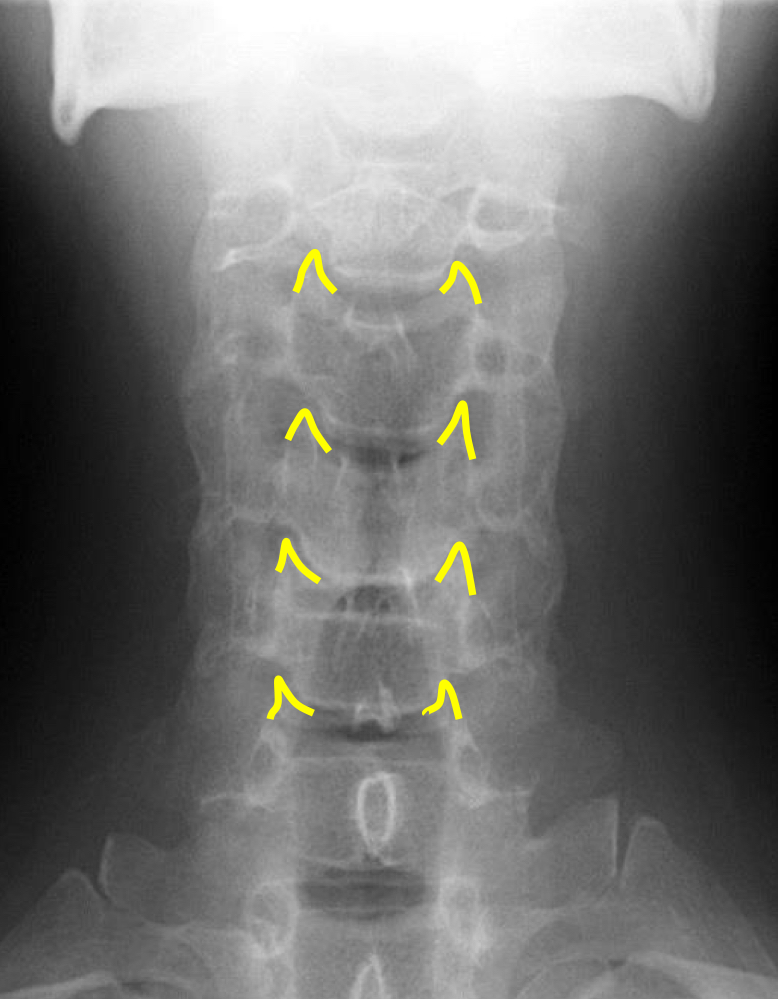

What view is this?

AP (Anterior to Posterior) Cervical

What is this?

Junction of Lamina/tip of Spinous

What is this?

Uncinate Processes

What is this?

Inferior Aspect of Vertebral Bodies